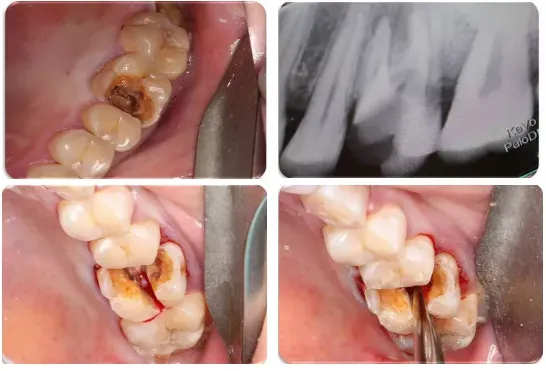

●通过图片和视频讲解各类下颌阻生第三磨牙的微创拔除方法

5、复杂的多根牙和单根牙也可以“简单”拔除;

●通过微创方法解决复杂的单根牙、多根牙